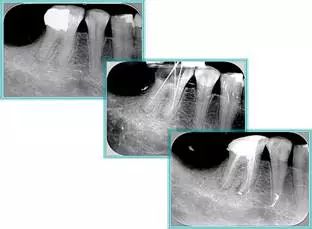

2. X 线片

共有 4 张 X 线片,分别是术前、诊断丝 、主牙胶尖确认、术后。

( 1 )术前:术前 X 线片用来了解牙齿的大概情况。术前预期为多根牙时 X 线片应偏头拍摄。

( 2 )诊断丝:根据术前 X 线片进行开髓、根管的初步预备后,需要插入诊断丝,用来指示工作器械位置。常用 10 号或 15 号扩大器作为诊断丝插入牙髓腔。

( 3 )主牙胶尖确认:通过术前预期和诊断丝诊断,明确工作长度、牙根走向,进行根管预备。之后应进行主牙胶尖(中锉)确认,已明确根管是否适合充填。

( 4 )术后:观察治疗效果。

3. 工作长度( WL )测量

应采用长度测量仪和诊断丝两种评估手段测量工作长度,减少误差。

测量过程中需要对根管进行全程初步疏通,从8号器械逐步疏通到20号器械, 08号 K → 10号 K → 10H → 15号K → 15 号 H → 20 号 K 。20号器械即根管的工作长度尖端直径是 0.20mm 。然后进行根管成形。

根管初步预备完毕后用 H 锉提拉,之后进行工作长度再确认。插上牙胶尖,拍摄 X 线片,观察主牙胶尖位置。